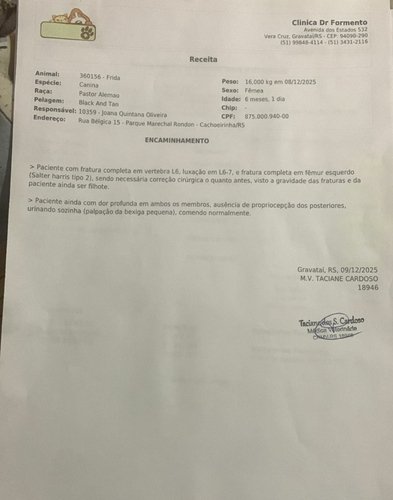

Atualmente, a Frida está sem conseguir ficar de pé, perdeu a sensibilidade da cauda e sente muita dor.

Mas há sinais reais de que ela pode recuperar os movimentos se operar agora:

- Ela ainda consegue urinar e defecar sozinha

- Tem movimento nos membros posteriores, mesmo com dificuldade

- É filhote, o que aumenta drasticamente a chance de regeneração

- Ou seja: a medula não está completamente rompida.

Com a cirurgia, ela tem uma chance concreta de voltar a andar.